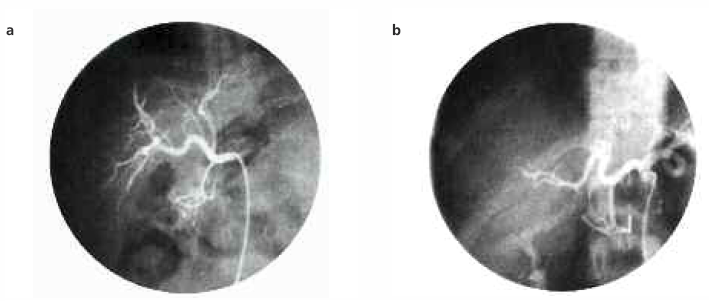

The child was prepared for cadaver liver transplantation and required blood transfusions and antibiotic therapy with good enteral feeding. He was discharged with some clinical improvement and put on the waiting list for a blood group A liver. Approximately 1 month later, the child was admitted with anemia (hemoglobin 7.0 g/dL) and a more-advanced hyperbilirubinemia (total bilirubin, 9.2 mg; direct bilirubin, 6.0 mg). It was during this time that the parents were informed about living-related partial liver donations. The mother, a 31-year-old woman with blood group A, volunteered to be the donor. Human leukocyte antigen (HLA) typing showed haploidentity, with the crossmatch being negative. The hematologic, biochemical, and urological analyses and the scintigraphic, radiologic, and tomographic evaluations of the donor showed no abnormality. Angiographic evaluation showed the recipient and donor hepatic and left hepatic arteries to be suitable (Figure la, b).

Figure 1. Normal hepatic angiograms for (a) the recipient and (b) donor.